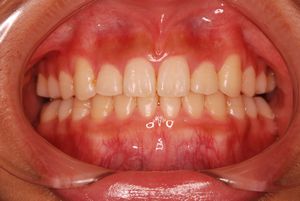

健康な小臼歯を抜いていません

矯正前                 矯正後

治療前 の 正面 です 動く矢印治療後 の 正面 です